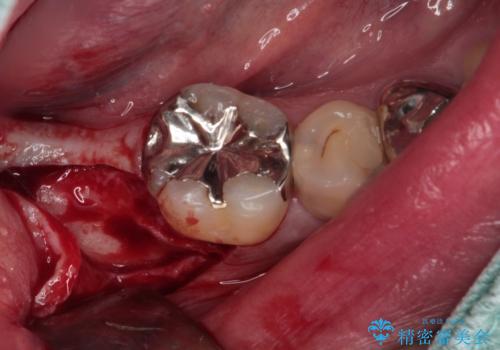

- 下顎左右の奥歯を治療途中で放置してしまっているとのことで来院された患者様です。

欠損部はインプラントによる補綴治療を、土台の外れてしまった歯は、根管治療を行った上で、補綴治療を行うこととしました。

骨格的に下顎が大きく上顎が小さいため、奥歯に力の負担のかかりやすい咬み合わせであるので、治療後は睡眠時にマウスピースを装着することで、セラミッククラウンやインプラント、治療をしたご自身の歯が長持ちするよう指導しています。